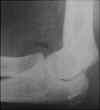

Case 2: A 13 year old boy fell while playing soccer.

Image 1:  This lateral radiograph of the elbow demonstrates a true lipohemarthrosis of the elbow joint. Again, there is a crescent shaped region of low density anterior to the radial head. This corresponds to fat which has migrated from the marrow space to the joint space through an intraarticular fracture. The fracture itself is not visible. CLICK TO ENLARGE.